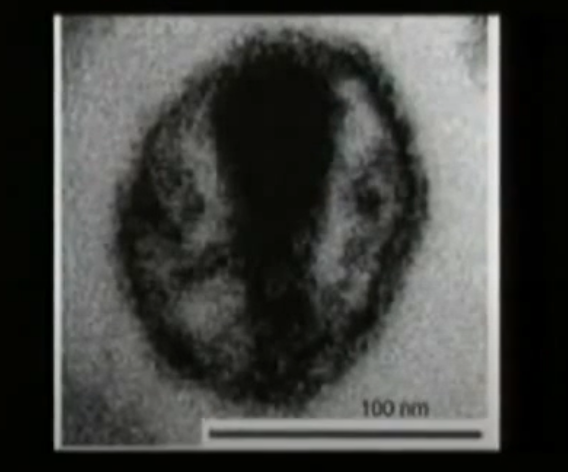

На представленной картинке, полученной с электронного микроскопа, мы видим вирус, окруженный липидной оболочкой, внутри которой находится его геном

Его размер очень маленький - 100 nm

По сравнению с песчинкой этот вирус такого же масштаба как песчинка по отношению к 3-х этажному дому.

На фото: вирион ВИЧ на изображении, полученном со сканирующего электронного микроскопа.